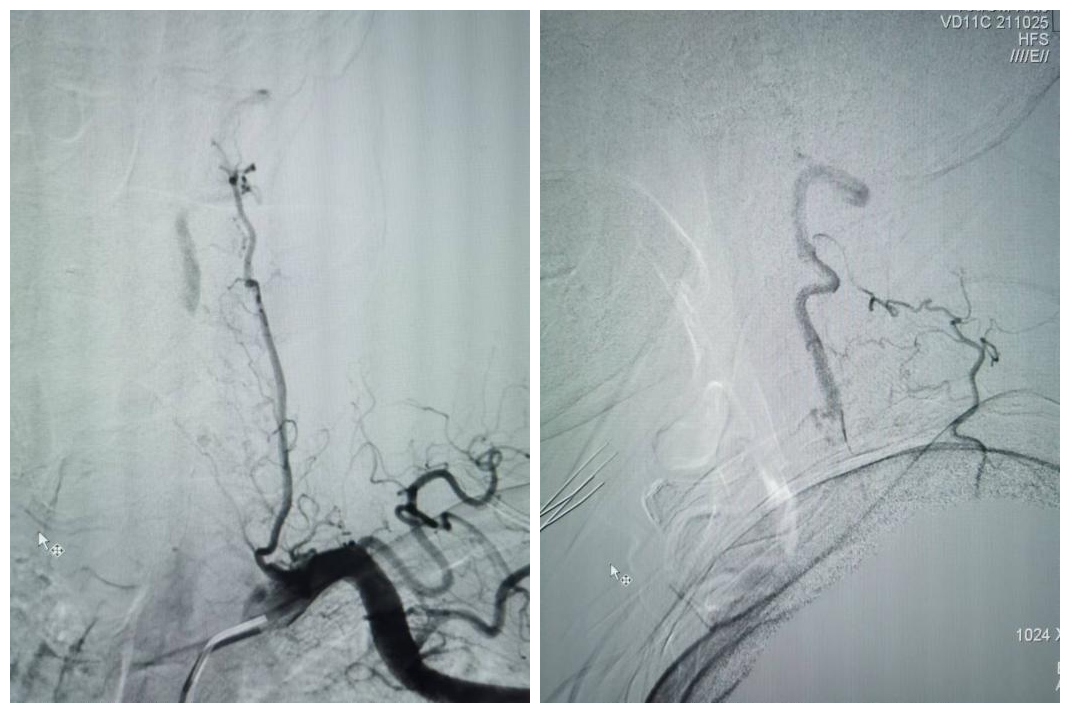

患者拜某,男,65岁,因反复头晕、晕厥1年,加重10天入院,既往5年前因心肌梗死在外院冠脉植入5枚支架。本次发病后当地医院发现患者脑后部的主干动脉——双侧椎动脉在颈部完全闭塞,当地医院药物医治无效,患者慕名从商洛来到我院神经内科。入院后经过脑血管造影发现患者双侧椎动脉颈部闭塞段大约10cm,闭塞远端经过甲状颈干及肋颈干向V2近颅底以远代偿供血,但因代偿不足,患者近来反复脑梗死2次,此次入院再次提示小脑新鲜脑梗死。

受呼吸起伏波动的影响,椎动脉开口狭窄是动脉粥样硬化好发的部位之一,也是支架成形术后支架内再狭窄的好发部位。这个短小的病变对于神经介入医师来说,常常是最青睐的支架手术部位。然而,该患者延伸至V2远端的长节段慢性闭塞病变,闭塞长度接近10cm,尤其是闭塞近段无残端的病变,常常会成为脑与心脏之间的“天堑”,使神经介入医师望而却步,即使眼看着患者的临床病情在进展,常常也是束手无策。

神经内科张桂莲教授带领的介入团队在影像科李晓会教授团队的鼎力支持下,反复查阅相关文献,尝试多种新型磁共振成像技术,最终历时4个小时,克服了肺内气体对磁共振成像质量的影响,通过特殊的MRI成像技术及体表定位技术,清晰显示出脑血管造影及高分辨核磁共振不能显示的闭塞的椎动脉开口,使之前无法完成的高难度手术变成可能。

最终,在患者入院第4天,张桂莲教授带领的介入团队选择局麻条件下为患者成功实施了神经介入领域的高难度手术—左侧无残端椎动脉长节段慢性闭塞再通术。因术前清晰的影像显影及准确的体外定位标记,左侧优势椎动脉顺利开通,手术耗时仅仅约90分钟。术中及术后患者配合良好,无任何不适,术后在介入准备室,张桂莲教授向患者女儿详细告知手术过程及患者目前状况,患者女儿喜极而泣,多次向介入团队表示感谢。